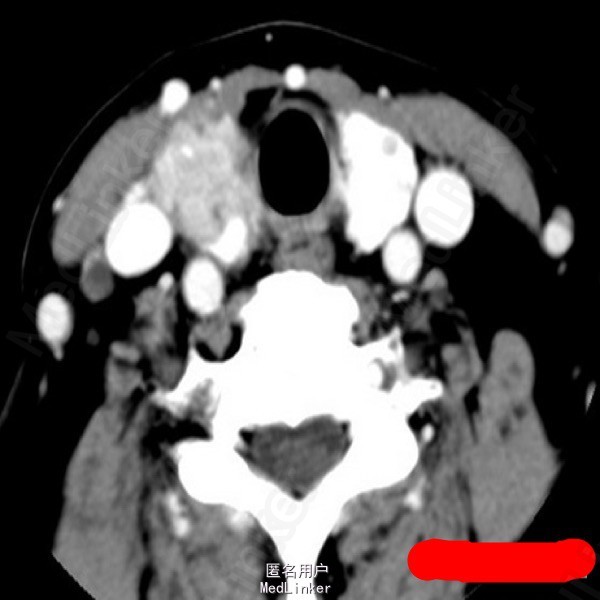

甲状腺癌

中年女性,发现颈部肿物半年,轻度吞咽困难1月。超声提示颈部可见甲状腺低回声结节,内见点状强回声。术后病理:甲状腺乳头状癌。问题:想问问大家对于甲状腺癌术后碘131治疗怎么看?